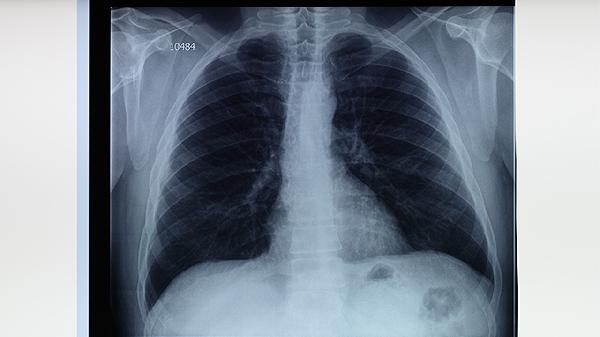

持续咳嗽咳痰超过2周、午后低热、夜间盗汗等症状出现时,需进行痰涂片检查和胸部X光筛查。确诊患者应严格完成6-8个月规范治疗,利福平片、异烟肼片、吡嗪酰胺片等药物联合使用可阻断传播链。密切接触者需接受结核菌素皮肤试验监测。